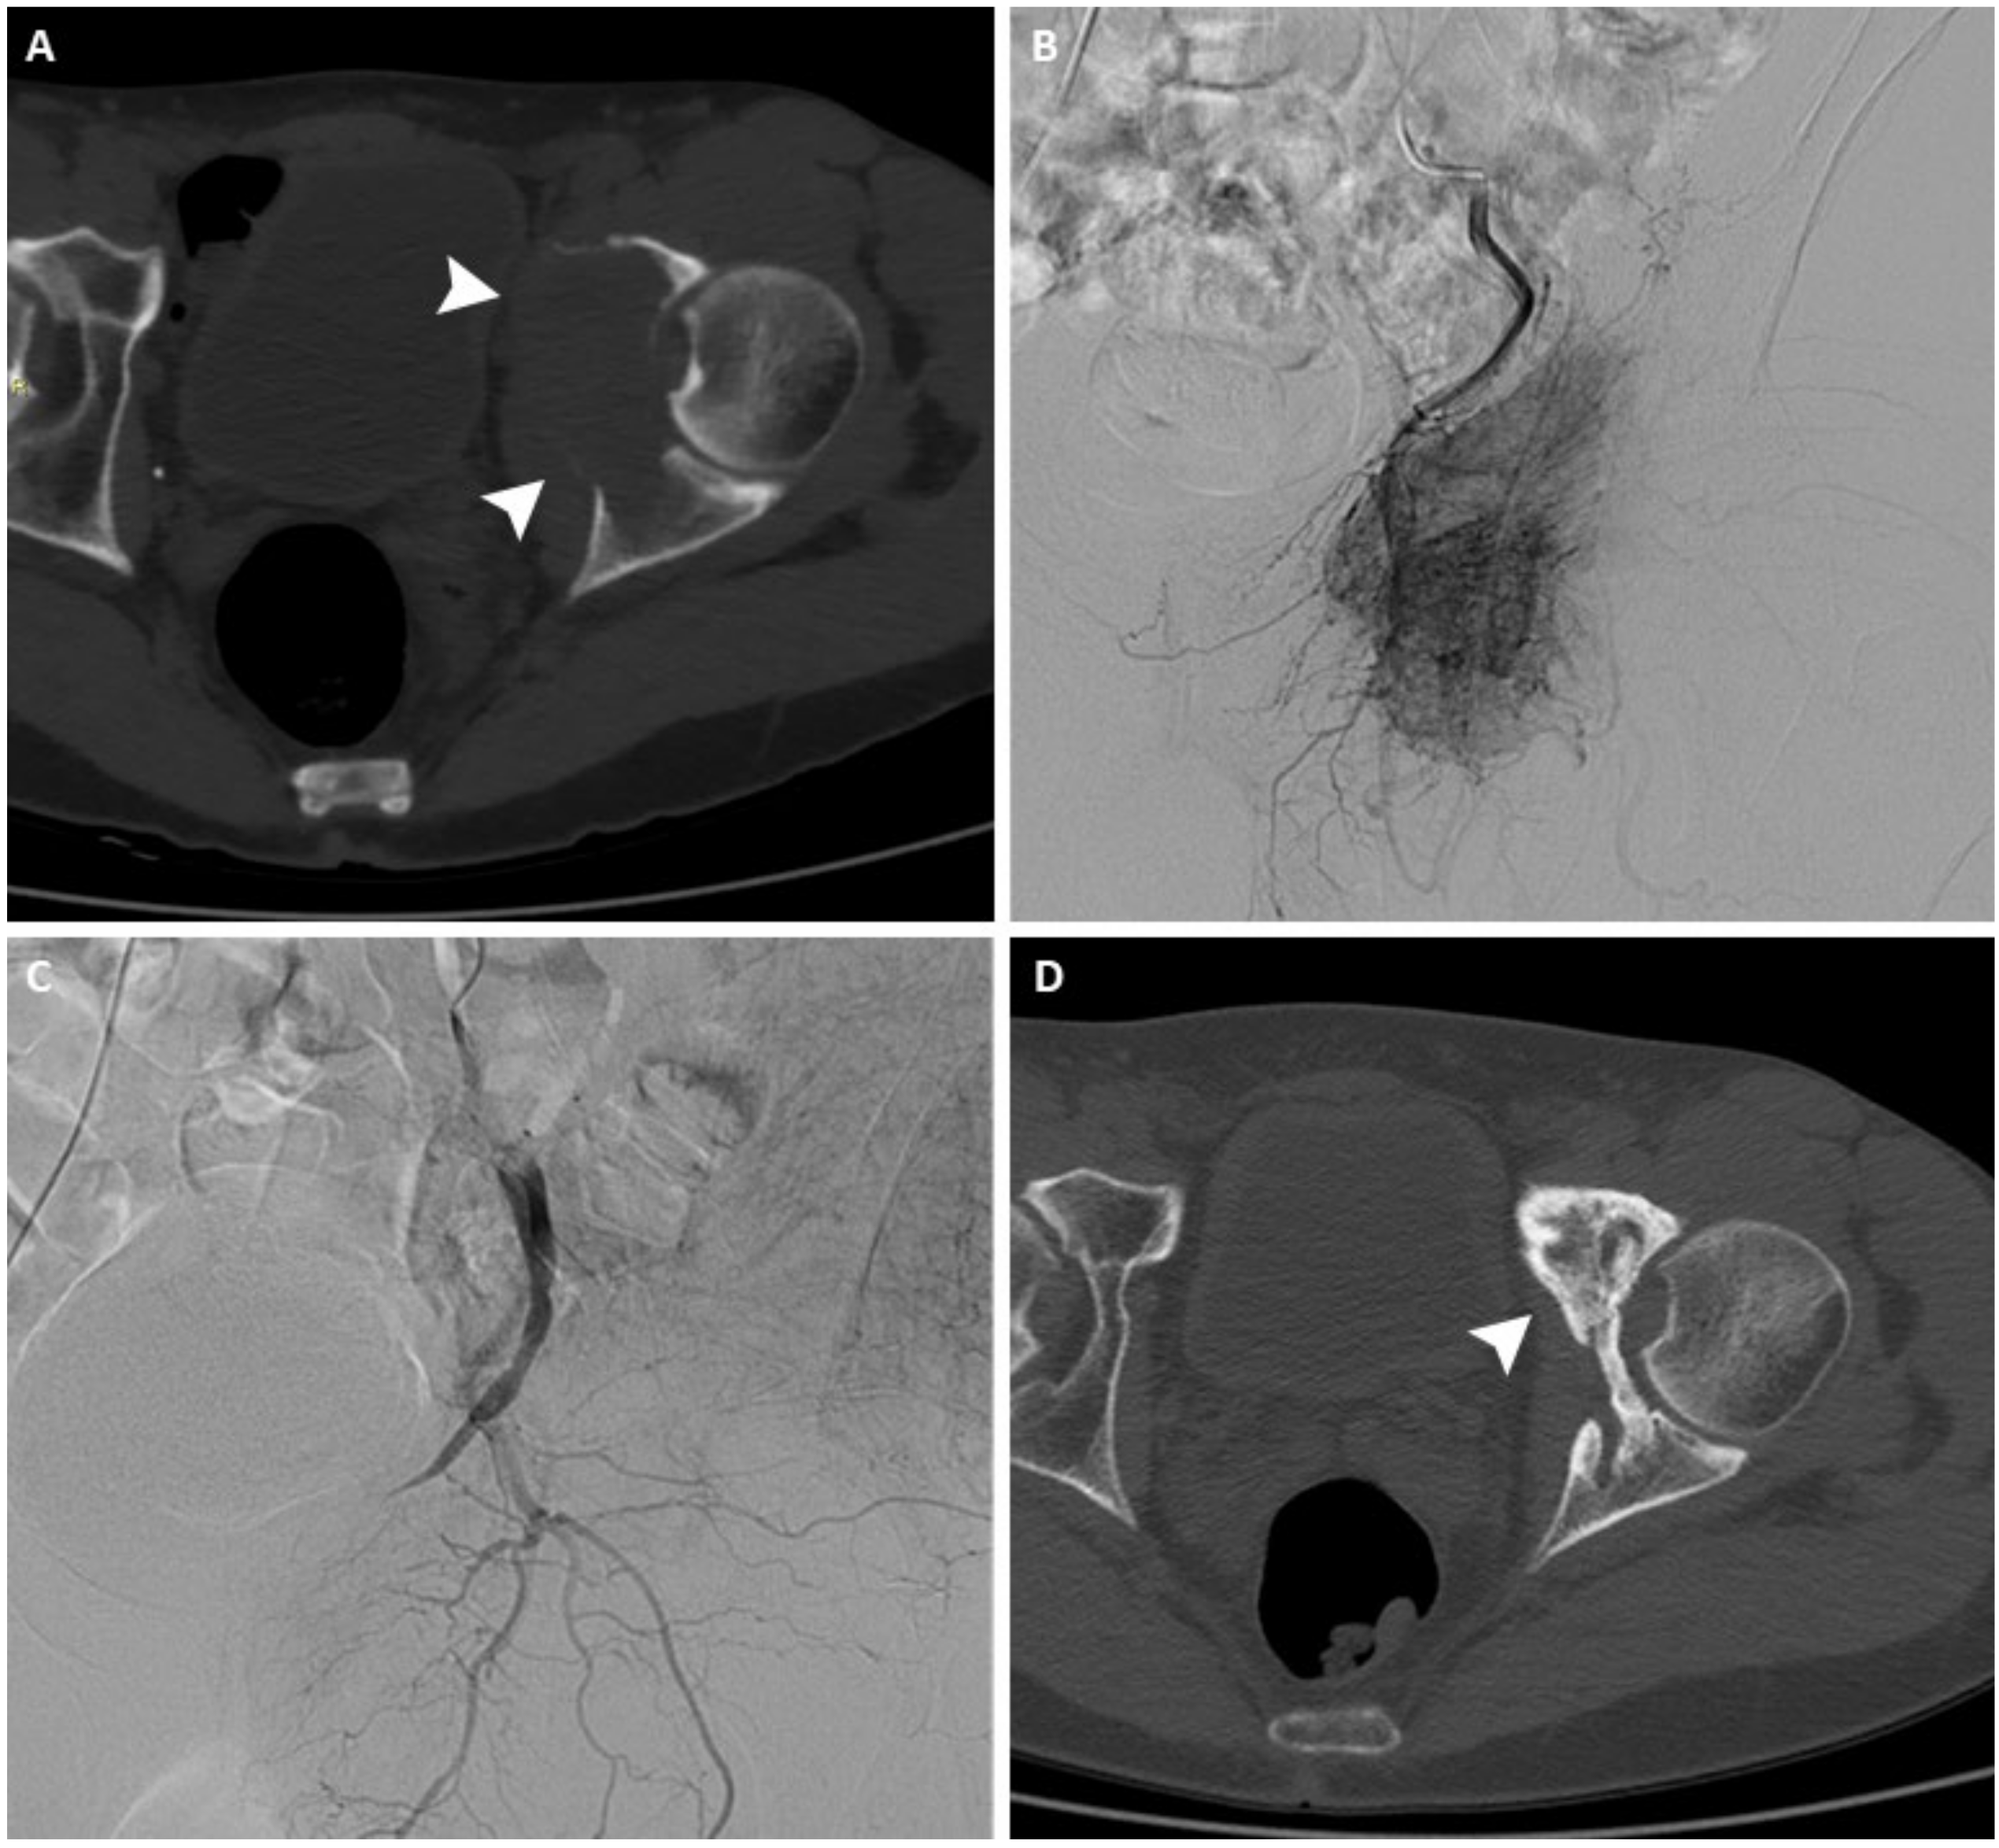

Figure 1.

(A) Axial CT scan of the pelvis of a 63-year-old man with a painful left acetabular bone metastasis from kidney cancer (arrowheads). (B) Arteriography shows pathological vascularization originating from branches of the internal iliac artery. (C) After arterial embolization, arteriography demonstrates complete occlusion of the feeding vessels. (D) Axial CT scan performed 12 months after treatment shows signs of re-ossification and local disease control (arrowhead).